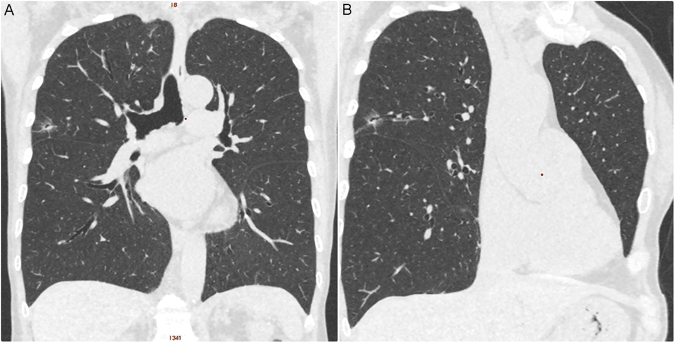

All scans were performed with a 16-slice CT (Somatom Sensation 16, Siemens Healthcare, Erlangen, Germany), a 64-slice CT (Aquilion 64; Toshiba Medical Systems), and 256-slice CT (Revolution CT, GE Healthcare, Milwaukee, USA) from the lung apex to the base without contrast enhancement. Images were reconstructed with a section thickness of 1–2.5 mm and displayed at a lung window width of 1600 HU, window level of −600 HU, and a mediastinal window width of 350 HU, with a window level of 35 HU. CT characteristics were retrospectively reviewed and analyzed by 2 experienced thoracic radiologists (FZW and MTW), with 9 and 30 years of experience in thoracic radiology, respectively. The imaging features for each nodule with pathologically proof were analyzed according to the following parameters: (1) lesion size, (2) solid part in a mediastinal window, (3) SSN subclassification into pure GGN, heterogeneous GGN (partly consolidated on lung windows), and part-solid nodules (with a mediastinal window solid component) according to the previous prospective study proposed by Kakinuma et al., (4) air-bronchogram (an example in Fig. 2), (5) abnormal cystic-like airspace (an example in Fig. 3), (6) Lung-RADS report of all SSNs, and (7) the attenuation values of pure and heterogeneous GGNs. Maximal diameters of the nodular lesion with solid components (in the maximal diameter when viewing using a mediastinal window setting) were measured on CT on axial images. The mean, minimum, and maximum CT attenuation expressed in HU was measured by placing a region of interest (ROI) of 15 mm2 on the lesion using a GE Advantage Server 2.0 (GE Healthcare). In addition, to avoid placing the ROI box in or near the blood vessels could reduce the measurement errors (examples in Figs 4 and 5).

Figure 5.

An example of heterogeneous GGN according to the SSN subclassification. A 66-year-old man had a 1.2 cm heterogeneous GGN nodule in RUL. The LDCT images showed heterogeneous groundglass opacities with focal solid component only when viewed on the lung window (Fig. 4A), but not seen on the mediastinal window (Fig. 4B). The average CT attenuation values (min, max and mean) expressed in HU were measured by placing an ROI of 15 mm2 on the lesion (Fig. 4C). In addition, to avoid placing the ROI box in or near the blood vessels could reduce the measurement errors. The patient underwent video-thoracoscopic wedge resection of RUL. Further pathologic report demonstrated invasive pulmonary adenocarcinoma in RUL. Abbreviations: GGN: groundglass nodule; SSN = subsolid nodule; RUL = right upper lobe; ROI = region of interest; HU = Hounsfield unit.